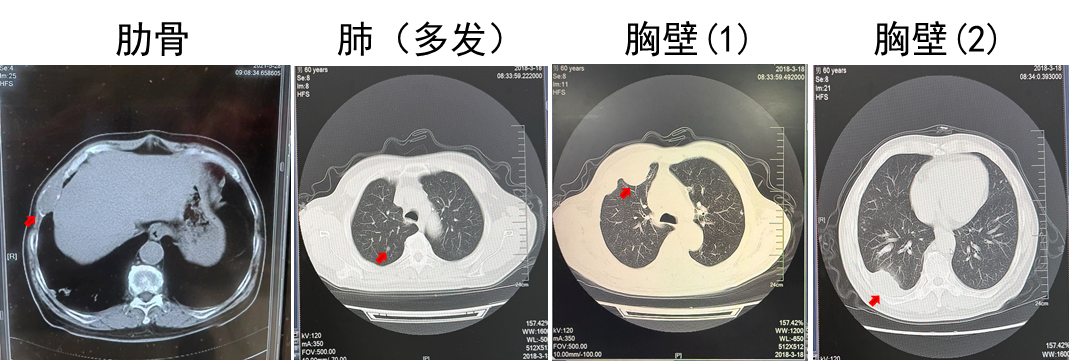

2018.03 PET-CT提示多发肺转移,肋骨转移

2018.03.22胸壁穿刺显示转移性癌,考虑肾来源

诊断为T2N0M1,IV期,IMDC低危

第二阶段:靶向治疗同步放疗

2018.03.22舒尼替尼50 mg QD。肋骨肿瘤注射唑来膦酸3周1次(共3次),同步放疗3 Gy(共10次)。

疗效:肋骨病灶疾病稳定(2年),肺部病灶部分缓解(2年)。

(舒尼替尼单药联合放疗,肋骨病灶实现SD)

(舒尼替尼单药联合放疗,肺转移病灶实现PR)